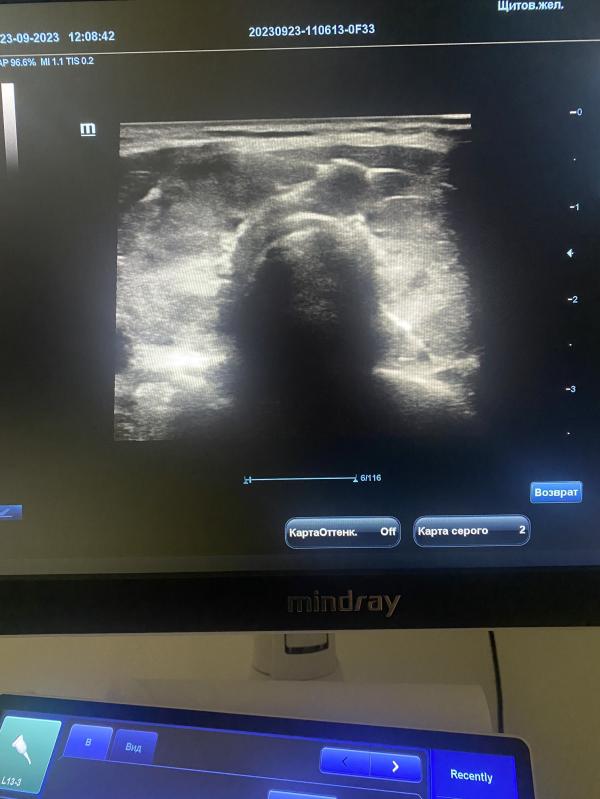

Распознать врага и вовремя обратиться к врачу помогут так называемые красные флаги – симптомы, наличие которых требует обязательного проведения УЗИ щитовидной железы.

Проведения УЗИ щитовидной железы рекомендуется 1 раз в год.